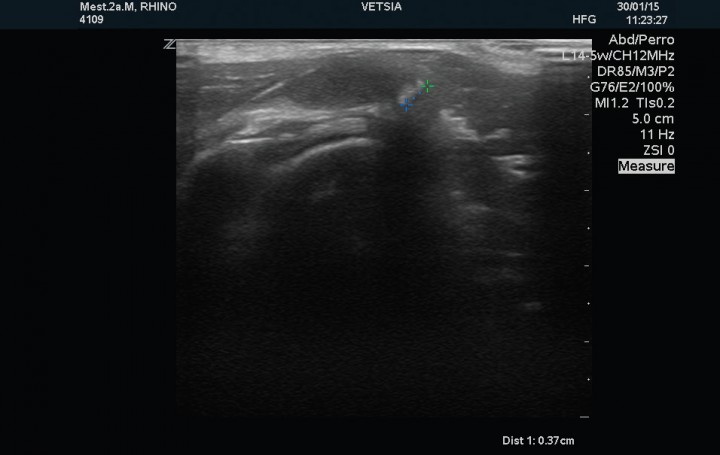

Se realizó examen ecográfico de ambas articulaciones escápulo-humerales con sonda lineal de 12 MHz; los hallazgos ecográficos observados en la articulación izquierda mostraron un tendón del músculo infraespinoso de estructura normal y 2,8 mm de grosor en corte transversal, el tendón del músculo supraespinoso presenta un grosor de 1,7 mm en su porción tendinosa, 4,2 mm en la transición fribrocartilaginosa y de 7,2 mm en la porción fibrocartilaginosa próxima al tubérculo mayor del húmero (zona de máximo grosor), evidenciándose en esta región, próxima a la superficie perióstica, una estructura ecogénica que producía una sombra acústica distal de 3,7mm de diámetro compatible con un foco de mineralización intratendinosa (Fig. 2). El tendón del músculo bíceps braquial presenta su inserción normal en la tuberosidad supraglenoidea con un grosor de 2,7 mm, mostrando su cápsula sinovial un engrosamiento en su porción más proximal (Fig. 3). La cabeza humeral y el cartílago articular se evidencian de contorno liso y grosor normal. La articulación escapulo-humeral derecha no presentaba ningúna alteracion (Fig. 4). La imagen ecográfica es compatible con tendinopatía del tendón del músculo supraespinoso, con mineralización en fibrocartílago de 3,7 mm y signos leves de sinovitis del bicipital.

<p>Corte sagital del tendón del músculo bíceps braquial izquierdo en el que se muestra una ligera distensión de la vaina sinovial y engrosamiento de la membrana sinovial.</p>

Figura 3

Corte sagital del tendón del músculo bíceps braquial izquierdo en el que se muestra una ligera distensión de la vaina sinovial y engrosamiento de la membrana sinovial.